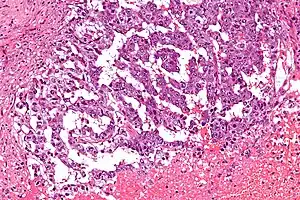

Micrograph showing the yolk sac component of a mixed germ cell tumour. H&E stain.

EST can have a multitude of morphologic patterns including: reticular, endodermal sinus-like, microcystic, papillary, solid, glandular, alveolar, polyvesicular vitelline, enteric and hepatoid.

Schiller–Duval bodies on histology are pathognomonic and seen in the context of the endodermal sinus-like pattern. Rarely, it can be found in the vagina.[5][6]